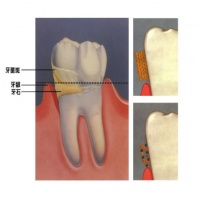

牙结石通常存在于唾液腺开口处的牙齿表面(例如:下颚前牙的舌侧表面,上颚后牙的颊侧表面)和牙齿的颈部,以及口腔粘膜运动不到的牙齿表面等处。牙结石开始时是软软的,会因逐渐的钙化而变硬。它是由75%的磷酸钙,15-25%的水、有机物、磷酸锰、矿酸钙及微量的钾、钠、铁所构成。并呈现出黄色、棕色、或者黑色。通俗地说:“牙结石即牙垢”,是附着在牙面上的矿化的菌斑和其他沉积物的总称。

牙结石对口腔而言是一种异物体,它会不断刺激牙周组织,并会压迫牙龈,影响血液循环,造成牙周组织的病菌感染,引起牙龈发炎萎缩,形成牙周囊袋。当牙周囊袋形成后,更易使食物残渣、牙菌斑和牙结石等的堆积,这种新的堆积又更进一步的破坏更深的牙周膜,如此不断的恶性循环的结果,终至牙周支持组织全部破坏殆尽,而使牙齿难逃拔除的恶运。

沉积在龈缘龈沟内的结石,对牙龈造成持续性的刺激和压迫,使牙龈组织发生局部营养障碍,抗菌能力降低,牙龈易出现炎症、出血、萎缩,严重时可引发牙周脓肿、牙齿松动、脱落,破坏牙列完整,妨碍咀嚼功能,加重消化道负担,影响机体健康。